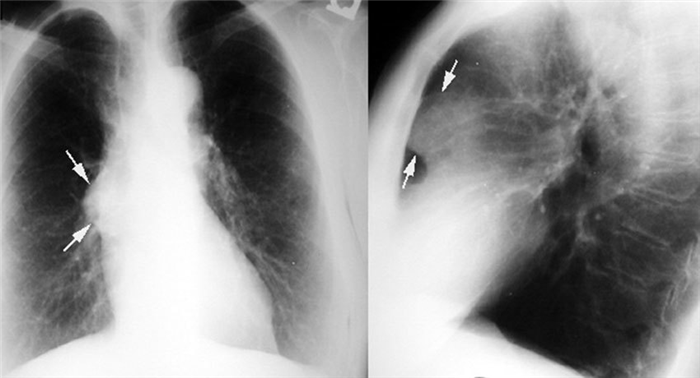

Хотя если этого нет, то на обзорных снимках очень сложно сказать, что это такое. Такое же овальное патологическое образование в переднем средостении. Контрастированный пищевод, который проходит по задней поверхности сердца и вдоль задней стенки трахеи.

Несмотря на очень большие размеры, оно длительное время может протекать бессимптомно. Важно, что почти всегда мы можем наблюдать связь со щитовидной железой. Это образование располагается в области верхней апертуры. Может быть в переднем или заднем средостении. Как правило, оттесняет и суживает трахею, что на рентгеновских снимках создает очень характерную типичную картину.

Если вы посмотрите на обзорный снимок в прямой проекции, то сразу же будет видно, насколько изменилась конфигурация воздушного столба в трахее на уровне грудино-ключичных расчленений и выше в области верхней апертуры. Трахея оттеснена по дуге вправо и практически достигает контура средостения и несколько сужена.

Большинство тимом можно обнаружить с помощью обычной рентгенографии. Опухоль выглядит как тень с ровными краями в верхней половине грудной клетки. Она частично перекрывает тень от сердца, находится преимущественно справа или слева.